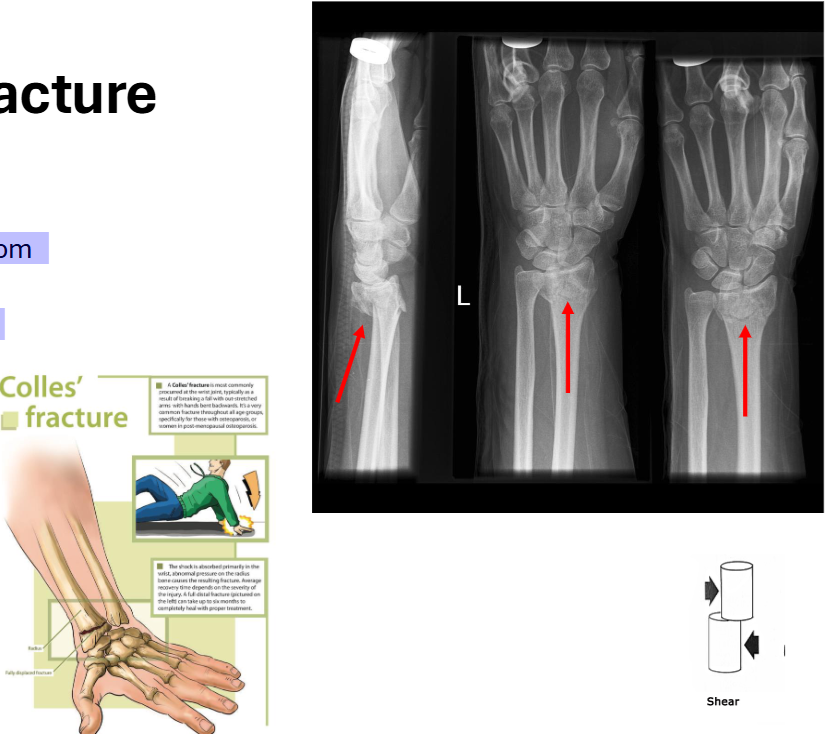

Special: Colles’ Fracture

Fracture of the distal radius

Comes from protecting oneself from a fall

Impacted fracture specific to the distal arm

Shearing force